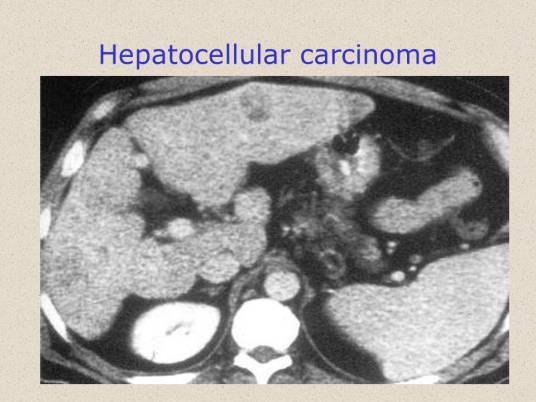

肝细胞性黄疸鉴别诊断需注意临床症状和体征,询问是否存在伴随症状,如发热、皮疹、皮肤瘙痒、乏力、食欲及尿粪异常、出血倾向以及各器官系统相应症状。查体应全面细致,不要有遗漏。特别注意皮肤黏膜黄染的颜色(溶血性黄疸常呈柠檬色,肝细胞性黄疽多为金黄色或浅黄色,阻塞性黄疸多为暗黄色或黄绿色)、淋巴结、肝胆脾有无肿大等。不同原发病体征不同,肝肿大并有门脉高压者多为肝硬化失代偿,肝癌并发黄疸患者体检可察肝肿大并伴有结节感,蜘蛛痣则见于慢性肝炎和肝硬化。肝细胞性黄疸的病程也可作为诊断的参考,如甲型、戊型病毒性肝炎的黄疸一般持续3~4周,乙、丙、丁型慢性肝炎的黄疸可以持续数月,或成为慢性肝内胆汁淤积。其他急性黄疸在病因解除或病变缓解后可于短期内消退,而癌肿引起的黄疸多呈进行性加重。